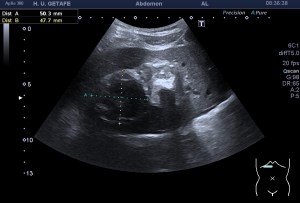

Al llegar al compartimento 6 me encuentro un tendón engrosado de tamaño y aspecto heterogéneo típico de afectación por tendinosis, con líquido en la vaina, te lo señala la imagen con flecha amarilla. Lo recorro y confirmo los hallazgos eje corto y eje largo, hago medidas y compruebo el doppler que marca Neovascularización asociada.

Observa las tres imágenes superiores, son muy ilustrativas, son comparativas de normalidad hallazgos patológicos, el izquierdo claramente patológico y el derecho claramente normal.